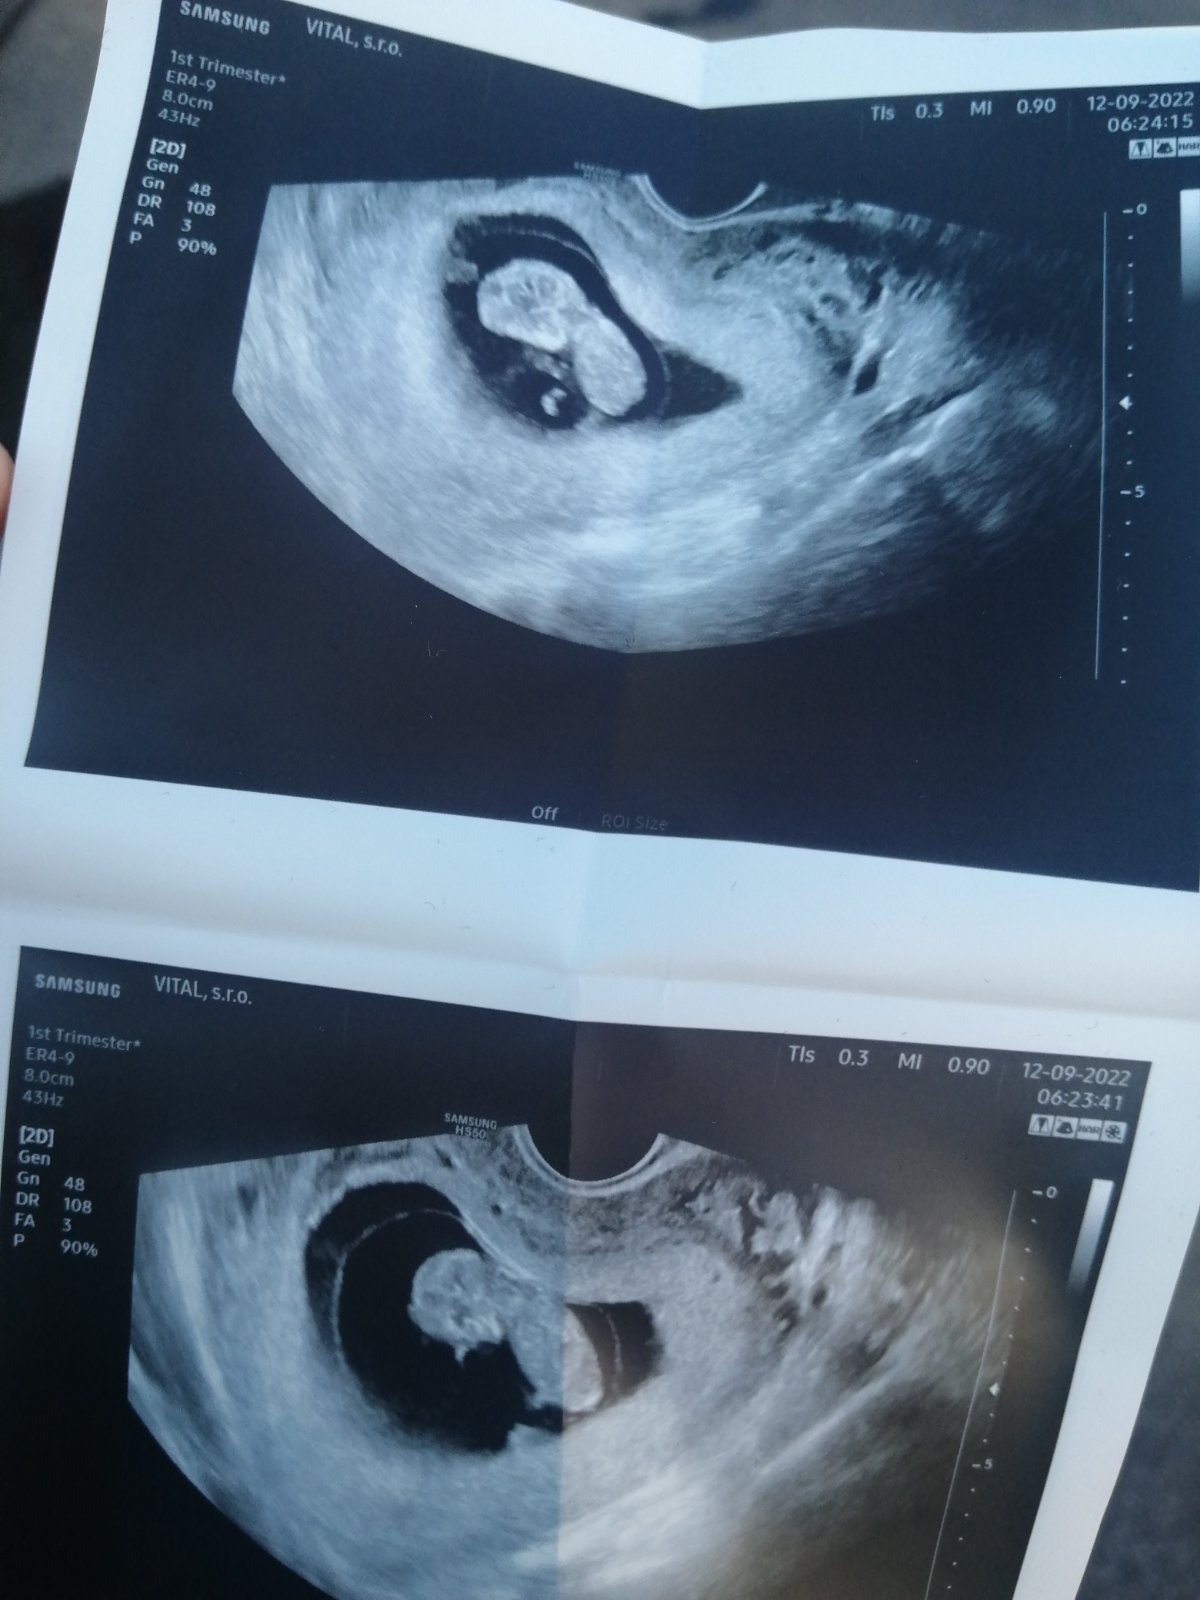

Je to nožička alebo pipík?

nie nie je to pipik 🙂 inak lekarka ti povie, ze to je noha ale tebe to neda...kolko ultrazvukov videla ona a kolko ty/my?

@whatever1 vieš kde sa nachádza pipík? Určite nie tam kde zobrazuješ a určite nie tam kde má pupočnú šnúru. Pipík je medzi nohami a určite by nebol taký veľký

@sunny_g hento není určite pupočna šnúra a dôverujem doktorovi ktorý sa zaoberá tým už 40rokov a nepomýlil sa ani raz 🙏

uvazuj a porovnaj hrubku a velkost... ak ma babatko par kg ako asi velkeho bude mat pipika?? urcite nie jak ruka hrubeho a "vyrastajuceho" z brusnej dutiny